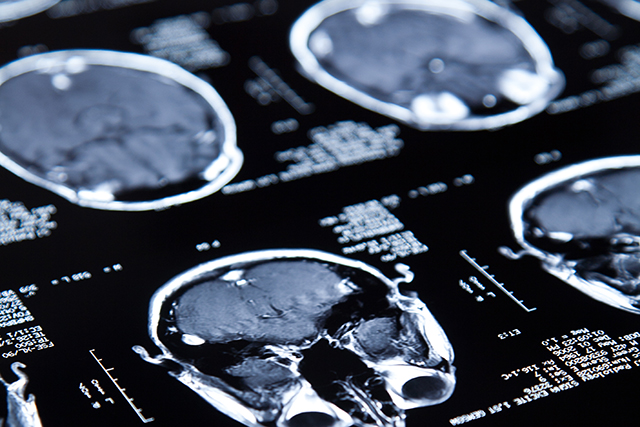

Brain tumors are complex, and biomarker testing is key to understanding the molecular makeup of a brain tumor, which can provide critical information about diagnosis, prognosis, and treatment options. Biomarker testing can also open doors to innovative treatment options for specific tumor types that are available only in clinical trials, which are often considered the best management for any patient with cancer. MyTumorID explains the importance of biomarker testing for patients with brain tumors and demystifies the often intimidating prospect of enrolling in a clinical trial for patients who are grappling with the worst news they may ever receive, “You have a brain tumor.”